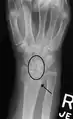

Dynamic instability: Increased scapholunate distance (between yellow lines) upon ulnar deviation of the wrist, but not otherwise.

Xray indicates scapholunate ligament instability when the scapholunate distance is more than 3 mm, which is called scapholunate dissociation.[7] A static instability is generally readily visible, but a dynamic scapholunate instability can only be seen radiographically in certain wrist positions or under certain loading conditions, such as when clenching the wrist, or loading the wrist in ulnar deviation.[6]